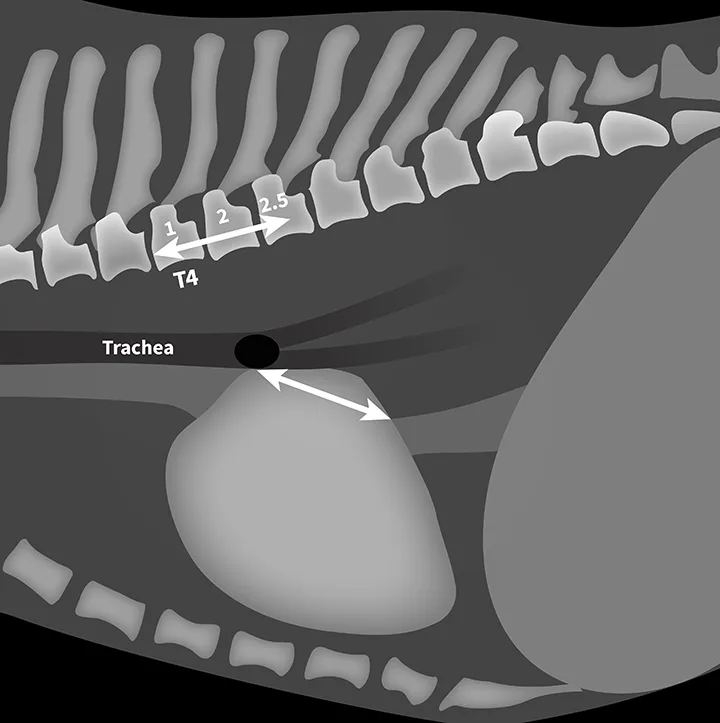

Step-By-Step: Measuring Vertebral Left Atrial Size

Step 1

Use calipers to measure from the center of the most ventral aspect of the carina to the most caudal aspect of the left atrium, where it intersects the dorsal border of the caudal vena cava, on the right or left lateral thoracic radiograph.

Step 2

Transfer the left atrial measurement to the cranial aspect of the fourth thoracic vertebrae (T4), extending caudally along the vertebrae at midbody position. Count the vertebrae transversed, and round to the nearest tenth (express the measurement, VLAS, in vertebral body units [VBUs]). VLAS is 2.5 in Figure 3.

FIGURE 3